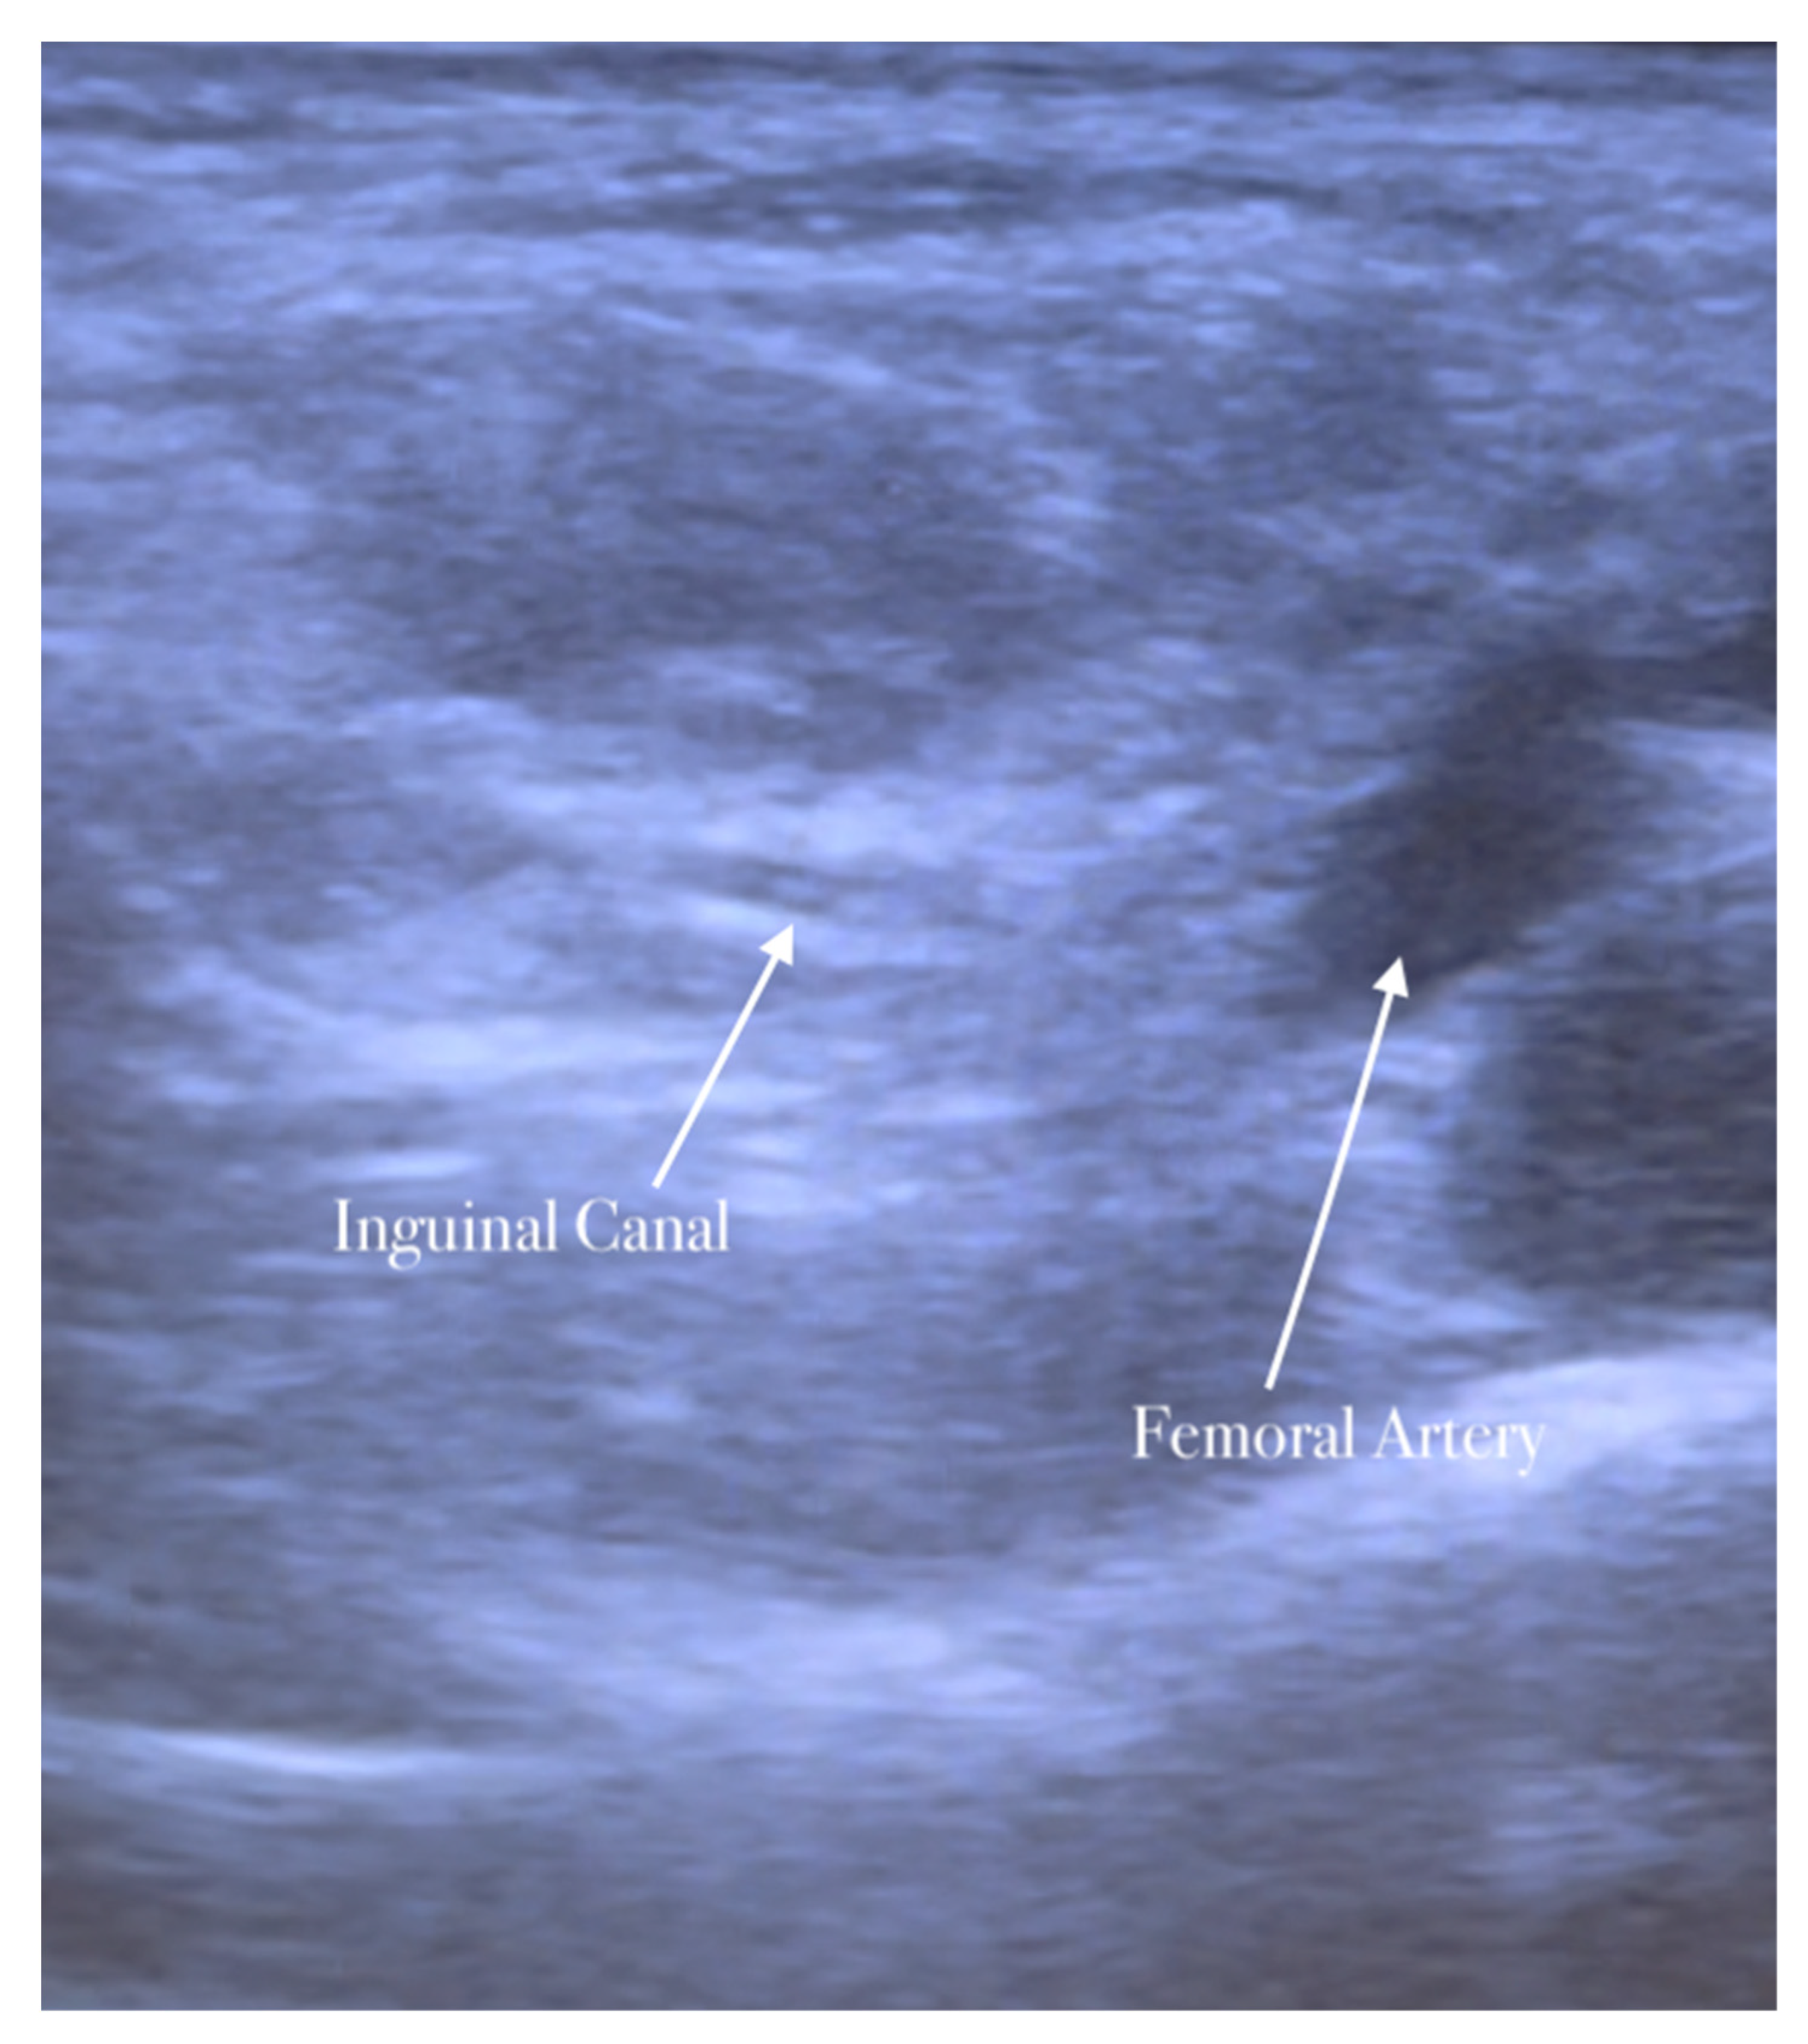

The second step of anesthesia consists of the genitofemoral nerve block. The genitofemoral nerve block decreases the pain induced by the traction of the hernia sac and improves the quality of analgesia for surgery in the inguinal region. The procedure is similar to the ilioinguinal–iliohypogastric nerves block. The genitofemoral nerve is formed from the first and second ventral rami of the lumbar nerve. It emerges on the anterior surface of the psoas major along the medial border, descends on the psoas major within the fascia iliaca, and crosses the posterior to the ureter and peritoneum. The nerve follows the lateral border of the common and external iliac artery. It is divided into genital and femoral branches above the inguinal ligament. The genital branch of the genitofemoral nerve passes through the transversalis and spermatic fascia before it enters the deep inguinal ring. It lies immediately laterally or deeply in the spermatic cord/round ligament and supplies the cremaster muscle [16,17].

The high-frequency linear probe is initially kept perpendicular to the inguinal ligament just above the femoral vessels. The final position of the probe is about 2 cm lateral to the pubic tubercle. In this position, the femoral artery is identified. The inguinal canal lies above and medially the femoral artery appearing as an oval or circular structure. The probe is then moved slightly in the medial direction away from the femoral artery.

The needle is inserted in the plane in a medial-to-lateral direction; 10 mL of anesthetic is injected in the transversus abdominis plane, as seen in Figure 5, Figure 6 and Figure 7.

Spermatic cord identification.